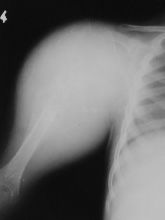

Osteosarkomların %75’i uzun kemiklerde özellikle diz bölgesinde ve kol kemiğinin üst ucunda görülür.

Klasik osteosarkom uzun kemiklerde kötü sınırlı, kemik yıkımına neden olan litik/sklerotik görünümlü lezyonlardır. Periostta kemiğe dik açıda oluşan kemik oluşumu (batan güneş manzarası) patogonomiktir. Yumuşak doku komponenti eşlik eder. BT kemik içerisindeki patolojileri göstermede yeterlidir. MRI ise yumuşak doku yayılımını, damar ve sinirin tutulup tutulmadığını, fiz hattının (büyüme kıkırdağı) etkilenip etkilenmediğini, komşu eklemin tutulup tutulmadığını, skip metastazların olup olmadığını ve uygun biyopsi yerinin belirlenmesinde yardımcıdır.